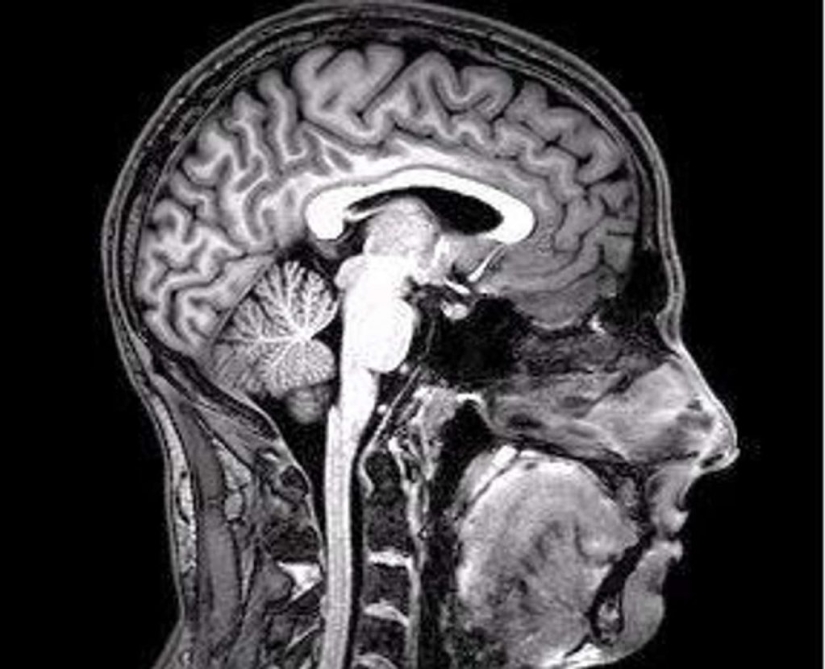

1. Fetal cells can remain with their mothers for years, even decades after the end of the pregnancy. These embryonic cells left behind are more than mere souvenirs from a baby; studies show that they can be used as an aid if the mother has suffered an injury such as a stroke. Louise McCullough, director of stroke research at the University of Connecticut Medical Center, conducted a study with colleagues that found that fetal cells can act like stem cells. McCullough studied fetal cells from mother mice that had suffered a stroke. These cells quickly found the area of the brain where the stroke had occurred, and within 72 hours the fetal cells surrounded the area of the clot.

6. Although yawning has traditionally been considered a sign of sleepiness or boredom, evolutionary psychologist Andrew Gallup says, "Recent evidence suggests that yawning may help cool the brain." This "cooling" effect occurs when you take a deep breath, stretching your jaw to increase blood flow, causing a downward flow of cerebrospinal fluid and blood from the brain. This allows the incoming air to slightly cool down liquids. And why are we doing this at night? According to Gallup, “At night, when we are about to go to bed, our brain and body temperatures reach their highest point during the day.”